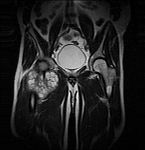

• Resection of benign and malignant tumors of the bone and soft tissue

• Extensive reconstructive procedures for the reconstruction of large pelvic bone defects